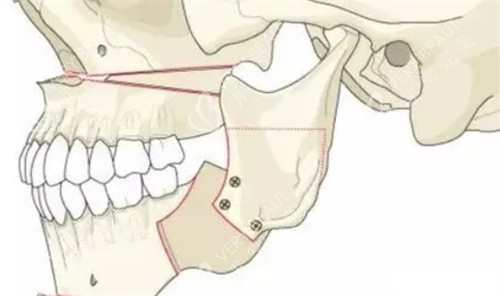

小创口截骨技术:采用特殊器械缩小截骨面积,减少组织损伤

医院采用CT导航辅助系统更好定位,配合自体脂肪移植调整面部平衡。

导航辅助截骨系统:实时影像引导确保截骨精度达0.1mm级

骨缝再生技术:特殊处理截骨边缘促进骨骼自然愈合